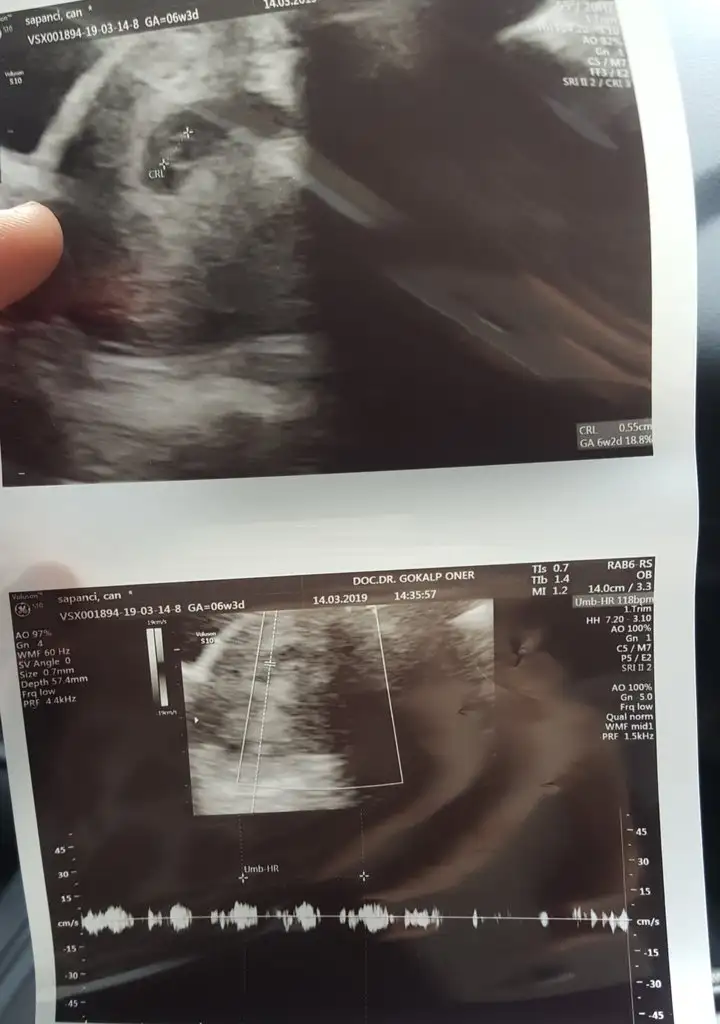

Seninkinede bir göz atarmısm canım ne yuvarlak ne uzun iyce yayvan şekilsiz bisey 😁😁

Evet vallah çok çektiriyor bazen midemin ağrısından hamile olduğumu unutup ağlıyorum 🤭 Dr. ilaç verdi ama bende panik atak var af buyur çıkaramadığım için devamlı boğuluyor hissi geliyordu çarpıntım oluyodu içmekten vazgeçtim. Şimdi mide yanması için şurup içiyorum inşallah bir hafta içinde geçer. Bu arada keseni gördüm yuvarlak değildi erkek gibi seninki de 😂 Benim de çok şekilsiz bir kesem var 🤔 istatistiklere göre şekilsizse erkek yuvarlaksa kız ama ne kadar doğru bilemedim 😂🤭